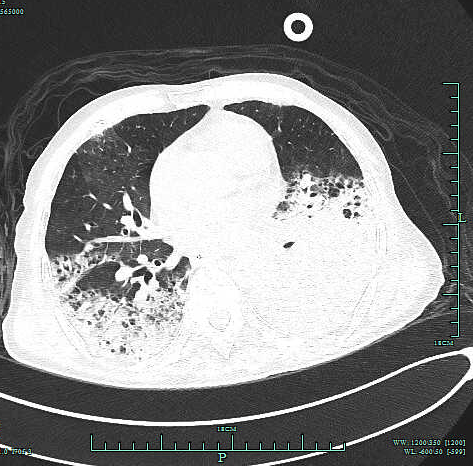

李琴(化名) , 女 , 47岁 , 因间断发热10天 , 胸闷、气喘加重1天收 住我院呼吸重症监护室 。 入院肺部CT提示两肺上叶、下叶背段多发感染 , 左肺下叶少许间质纤维化伴间质性炎症 , 两侧胸腔积液 。 入院予以无创辅助通气(高流量氧支持) ,积极抗感染、补液、纠正内环境等对症支持治疗 , 效果欠佳 , 在院期间完善痰、尿、便检验及院外肺泡灌洗液NGS , 均未寻找到可靠病原学依据来指导临床 。鉴于患者病情危重 , 治疗效果不理想 , 感染病因难以明确 , 预后较差 , 经 家属同意 , 医师在床旁行“超声定位引导下右肺穿刺活检术” , 后期 随访病理诊断:机化性肺炎 。 后经系统治疗患者临床症状改善 , 好转出院 。